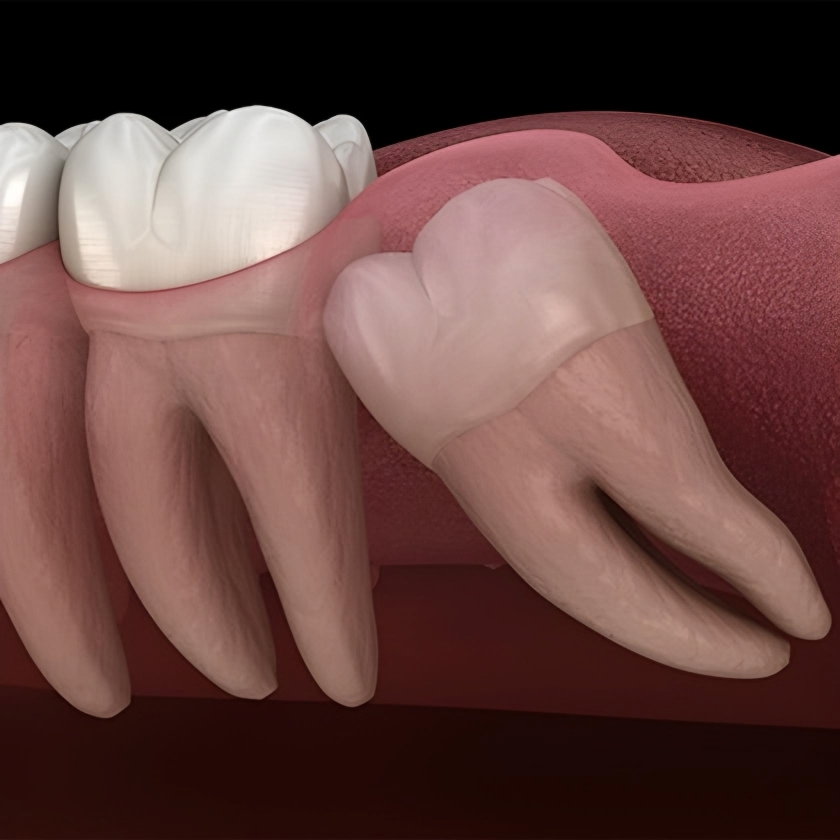

برخی مواقع که دندان عقل به صورت ناقص رشد میکند و گاهی نیز شکل طبیعی ندارد و محل آن نیز مساعد نیست در این صورت دندان عقل میتواند مشکلاتی ایجاد کند که باید کشیده و یا جراحی دندان عقل انجام شود، ولی در حالتی که وضعیت دندان عقل نرمال باشد و جایگاه آن نیز مشکلی نداشته باشد، نیازی به کشیدن ندارد. دندان عقل در عمیقترین جای دهان بوده و دسترسی به آن سخت است. به همین دلیل تمیز نگه داشتن آن مشکل بوده و پوسیدگی در آن زیاد مشاهده میشود. دندان نهفته دندانی است که به علت ممانعت دندانهای مجاور، تنگی فک و کمبود فضای لازم تراکم و سفتی بیش از حد استخوان در زمان معین و خاص خود رویش نیافته.

اگر دندان عقل جای کافی برای رشد نداشته باشد یعنی نهفته یا نیمه نهفته باشد باید با جراحی این دندان را خارج کرد.

جراحی دندان نهفته

دندان نهفته به دندانی گفته می شود که به علت کوچک بودن فک و کمبود فضا، نامتناسب بودن قوس دندانی، تراکم غیر طبیعی استخوان و یا مزاحمت و اشغال فضا توسط دندانهای مجاور، در زمان مناسب رشد نمی کند و معمولاً روی آن با استخوان، بافت مخاطی و یا هر دو پوشیده می شود. ضرورت اقدام برای خارج کردن دندانهای نهفته به این دلیل است که با افزایش سن احتمال ابتلا به بیماریهای قلبی و ریوی، فشار خون، بیماری قند، بیماریهای سیستم ایمنی، فک جوش شدن، عدم انعطاف کافی استخوان فک و روند کند ترمیم استخوان و مخاط، خارج کردن این دندانها را پیچیده می کند.